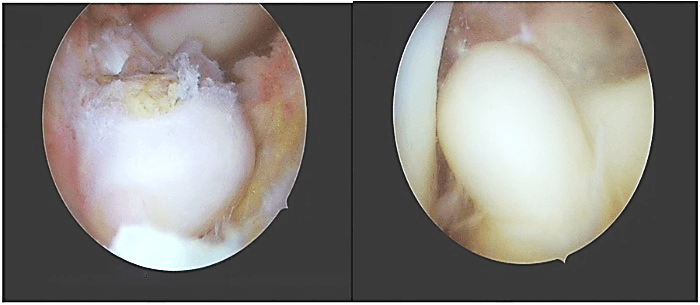

Figure 2: Macroscopic appearance of single white-brownish rubbery oval mass located on the tibial attachment of anterior cruciate ligament, measuring about 15×10 mm.

Arthroscopic examination showed an oval-shaped rubbery mass, measuring about 15mm×10mm in diameter, white-brownish in color, located at the tibial attachment of the ACL, and no other masses were found (Figure 2). The single lesion was excised using a shaver and bipolar radiofrequency ablation device. Further arthroscopic examination showed an intact cruciate ligament, menisci, and cartilage. Histopathological examination revealed the presence of mononuclear cells with scattered multinucleated giant cells and foci of fibrous stroma (Figure 3).